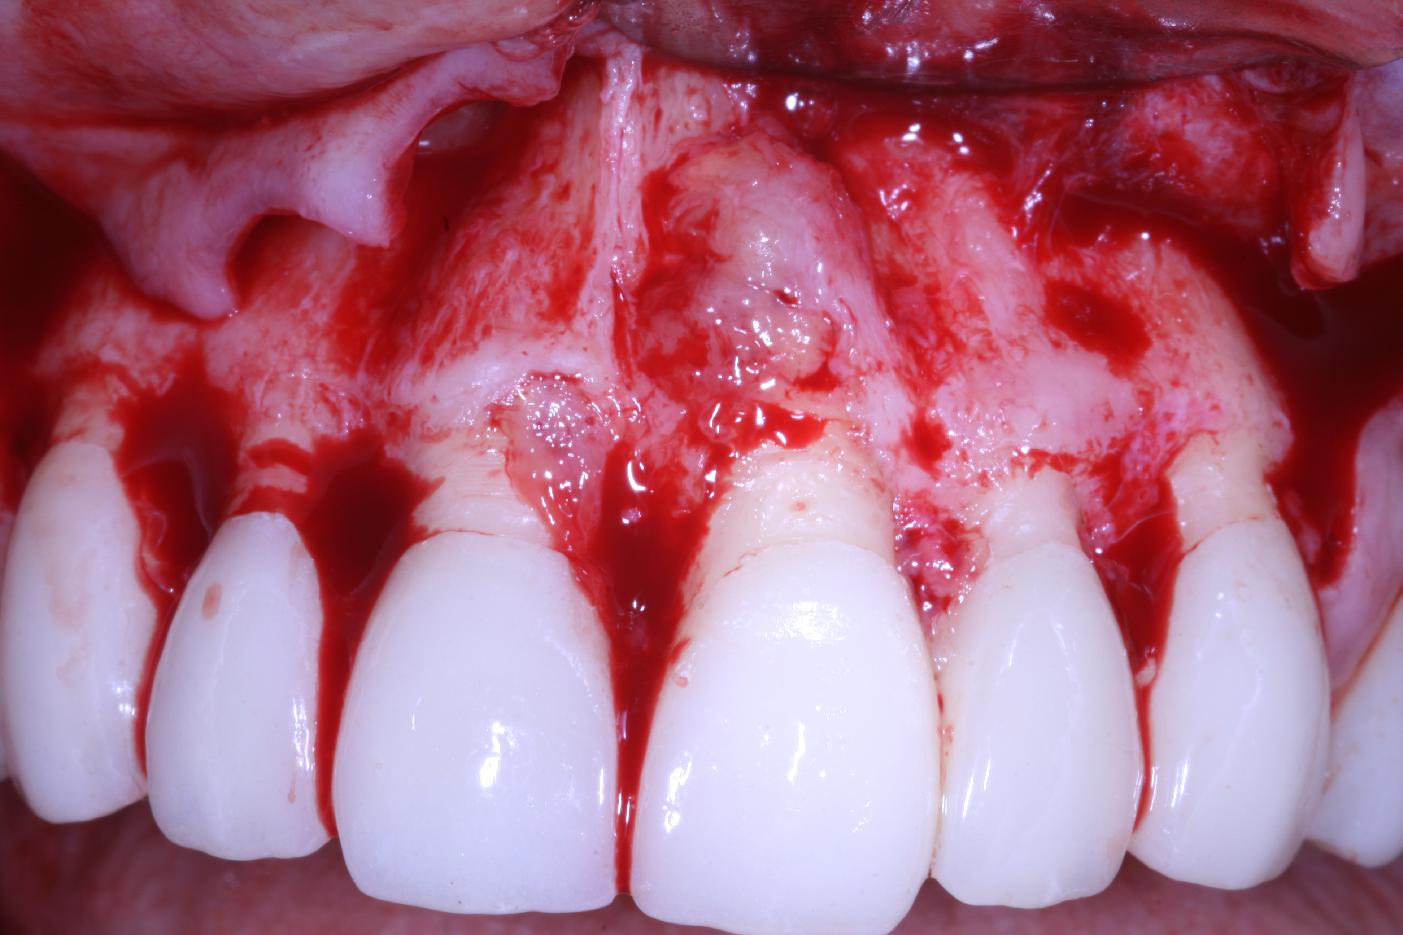

Mucosal thickening around bone level implants - Dr. A. Puisys

Full-thickness flap preparation bucally and lingually